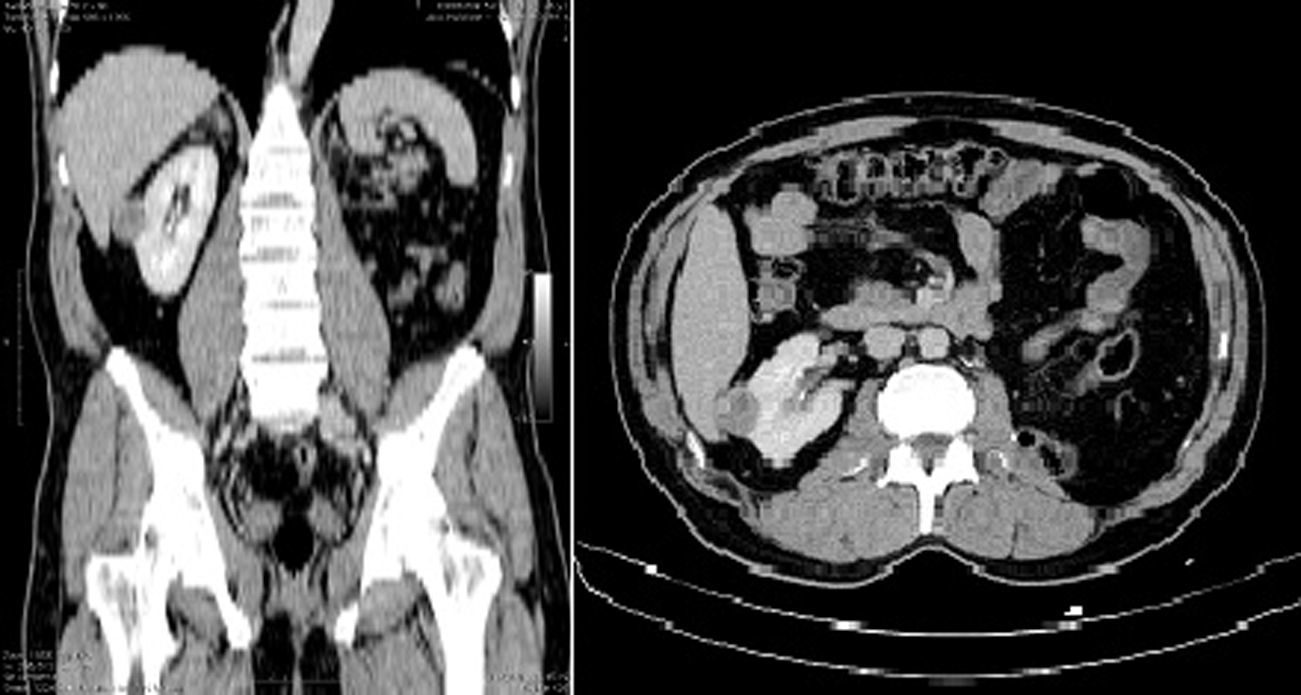

Una vez seleccionados, se calculó el puntaje de acuerdo al sistema de nefrometría R.E.N.A.L. con la revisión de los estudios imagenológicos correspondientes (35 tomografías con contraste y 3 resonancias magnéticas contrastadas). Es conveniente recordar los parámetros imagenológicos valorados por el sistema R.E.N.A.L. y el puntaje calculado por cada variable (fig. 1):

Se efectuó la subdivisión en 3 subgrupos de acuerdo al puntaje R.E.N.A.L.: baja complejidad (de 4-6; n=21); moderada complejidad (de 7-9; n=14), y alta complejidad (de 10-12; n=3). La muestra estuvo constituida por 20 mujeres y 18 hombres. La media de edad fue de 53 años. Quince pacientes fueron sometidos a nefrectomía parcial por laparoscopia y 23 con abordaje abierto. La figura 2 ejemplifica el análisis tomográfico tenido en cuenta para establecer la complejidad de los tumores evaluados.